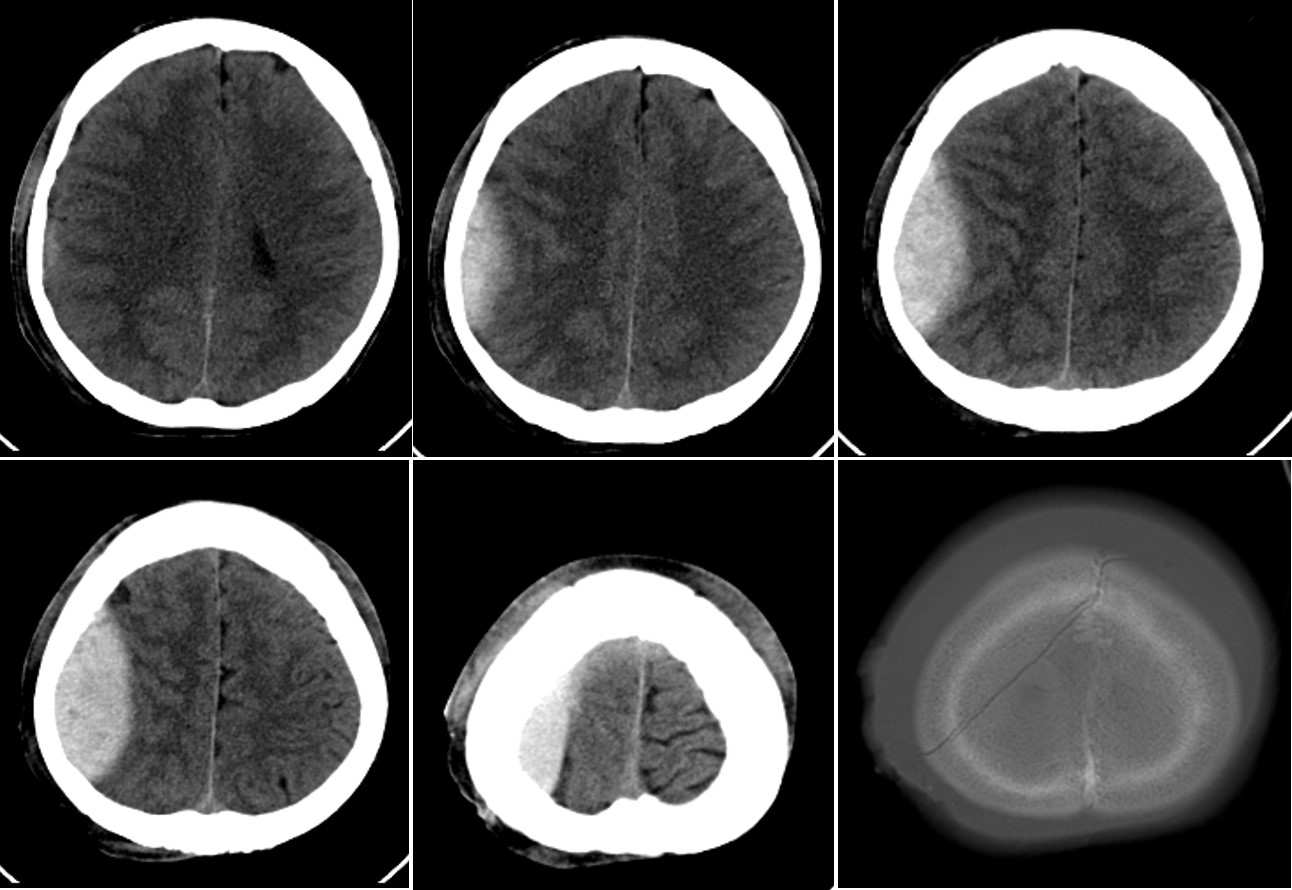

Head CT scan of a patient complaining of headache after motor vehicle accident

A 55-year-old man involved in a motor vehicle accident complains of headache, his GCS is 14/15.

What’s the diagnosis ?